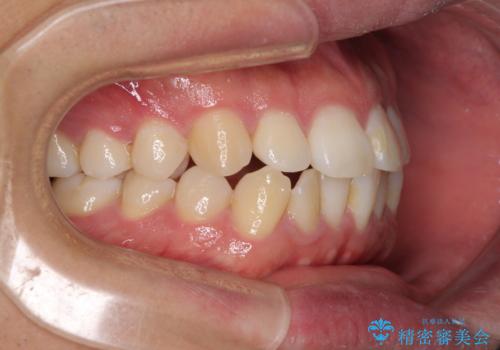

インビザラインで奥歯の咬み合わせと前歯のデコボコを改善

- 前歯のデコボコと奥歯の咬み合わせを気にして来院された患者様です。

前歯のデコボコはインビザラインで十分に対応可能と判断できましたが、咬合力が強いため、臼歯(特に右側)の交叉咬合はインビザライン単体では困難と思われました。

まずはインビザライン単体で矯正治療を開始し、交叉咬合が改善されない場合にはアンカースクリューなどの使用を検討することとしました。

インビザライン単体では右側の交叉咬合を解消することができなかったため、アンカースクリューを併用して咬合を改善させました。